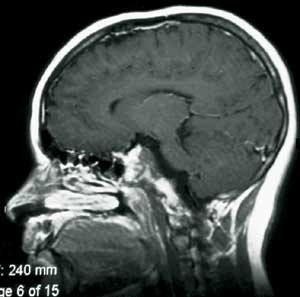

De siste tiårs etablering av multidisiplinære kraniofacialteam og transfaciale teknikker har gitt kirurgisk tilgang til mediale deler av hjernens basis og stamme fra sella turcica og ned til 4. halsvirvel (fig 1). Mens en transnasal, transsfenoidal tilgang vil være velegnet for lesjoner nær sella turcica (6), vil man ofte velge en transmaksillær, transfaryngeal tilgang for lesjoner i clivusområdet (7, 8) transoralt for lesjoner nær kraniocervikalovergangen (9) og endog transmandibulært for lesjoner kaudalt for dette (7).

Under mikroskop åpnes deretter svelgveggen ved en midtlinjeincisjon gjennom alle lagene. Den beinete bakveggen fridissekeres subperiostalt, og ved bruk av høyhastighetsdrill fjernes deler av skallebasis i ønsket omfang inntil man kommer inn mot dura (fig 1).

De siste tiårs utvikling av multidisiplinære kraniofacialteam har gjort det mulig å angripe lesjoner beliggende i de sentrale, mediale sonene av skallens basis i fremre og midtre skallegrop nedenfra via transfaciale tilganger (fig 1). Vi har presentert to pasienter med svulster i clivus som ble operert ved hjelp av slike teknikker.